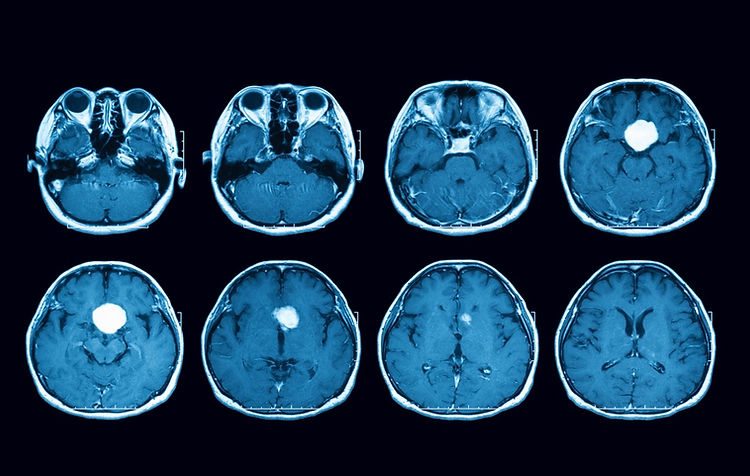

Oh my god, there were so many tests. I did a cat-scan and an MRI. Then, I had to go to have a Venus trapping which is when they put tubes from my groin all the way to my brain. After all the tests, the specialist diagnosed me.

I had a pituitary tumor that was at the base of the brain, touching the optic nerve. It was about the size of an orange. The doctors said that another month I would have been blind in one eye.